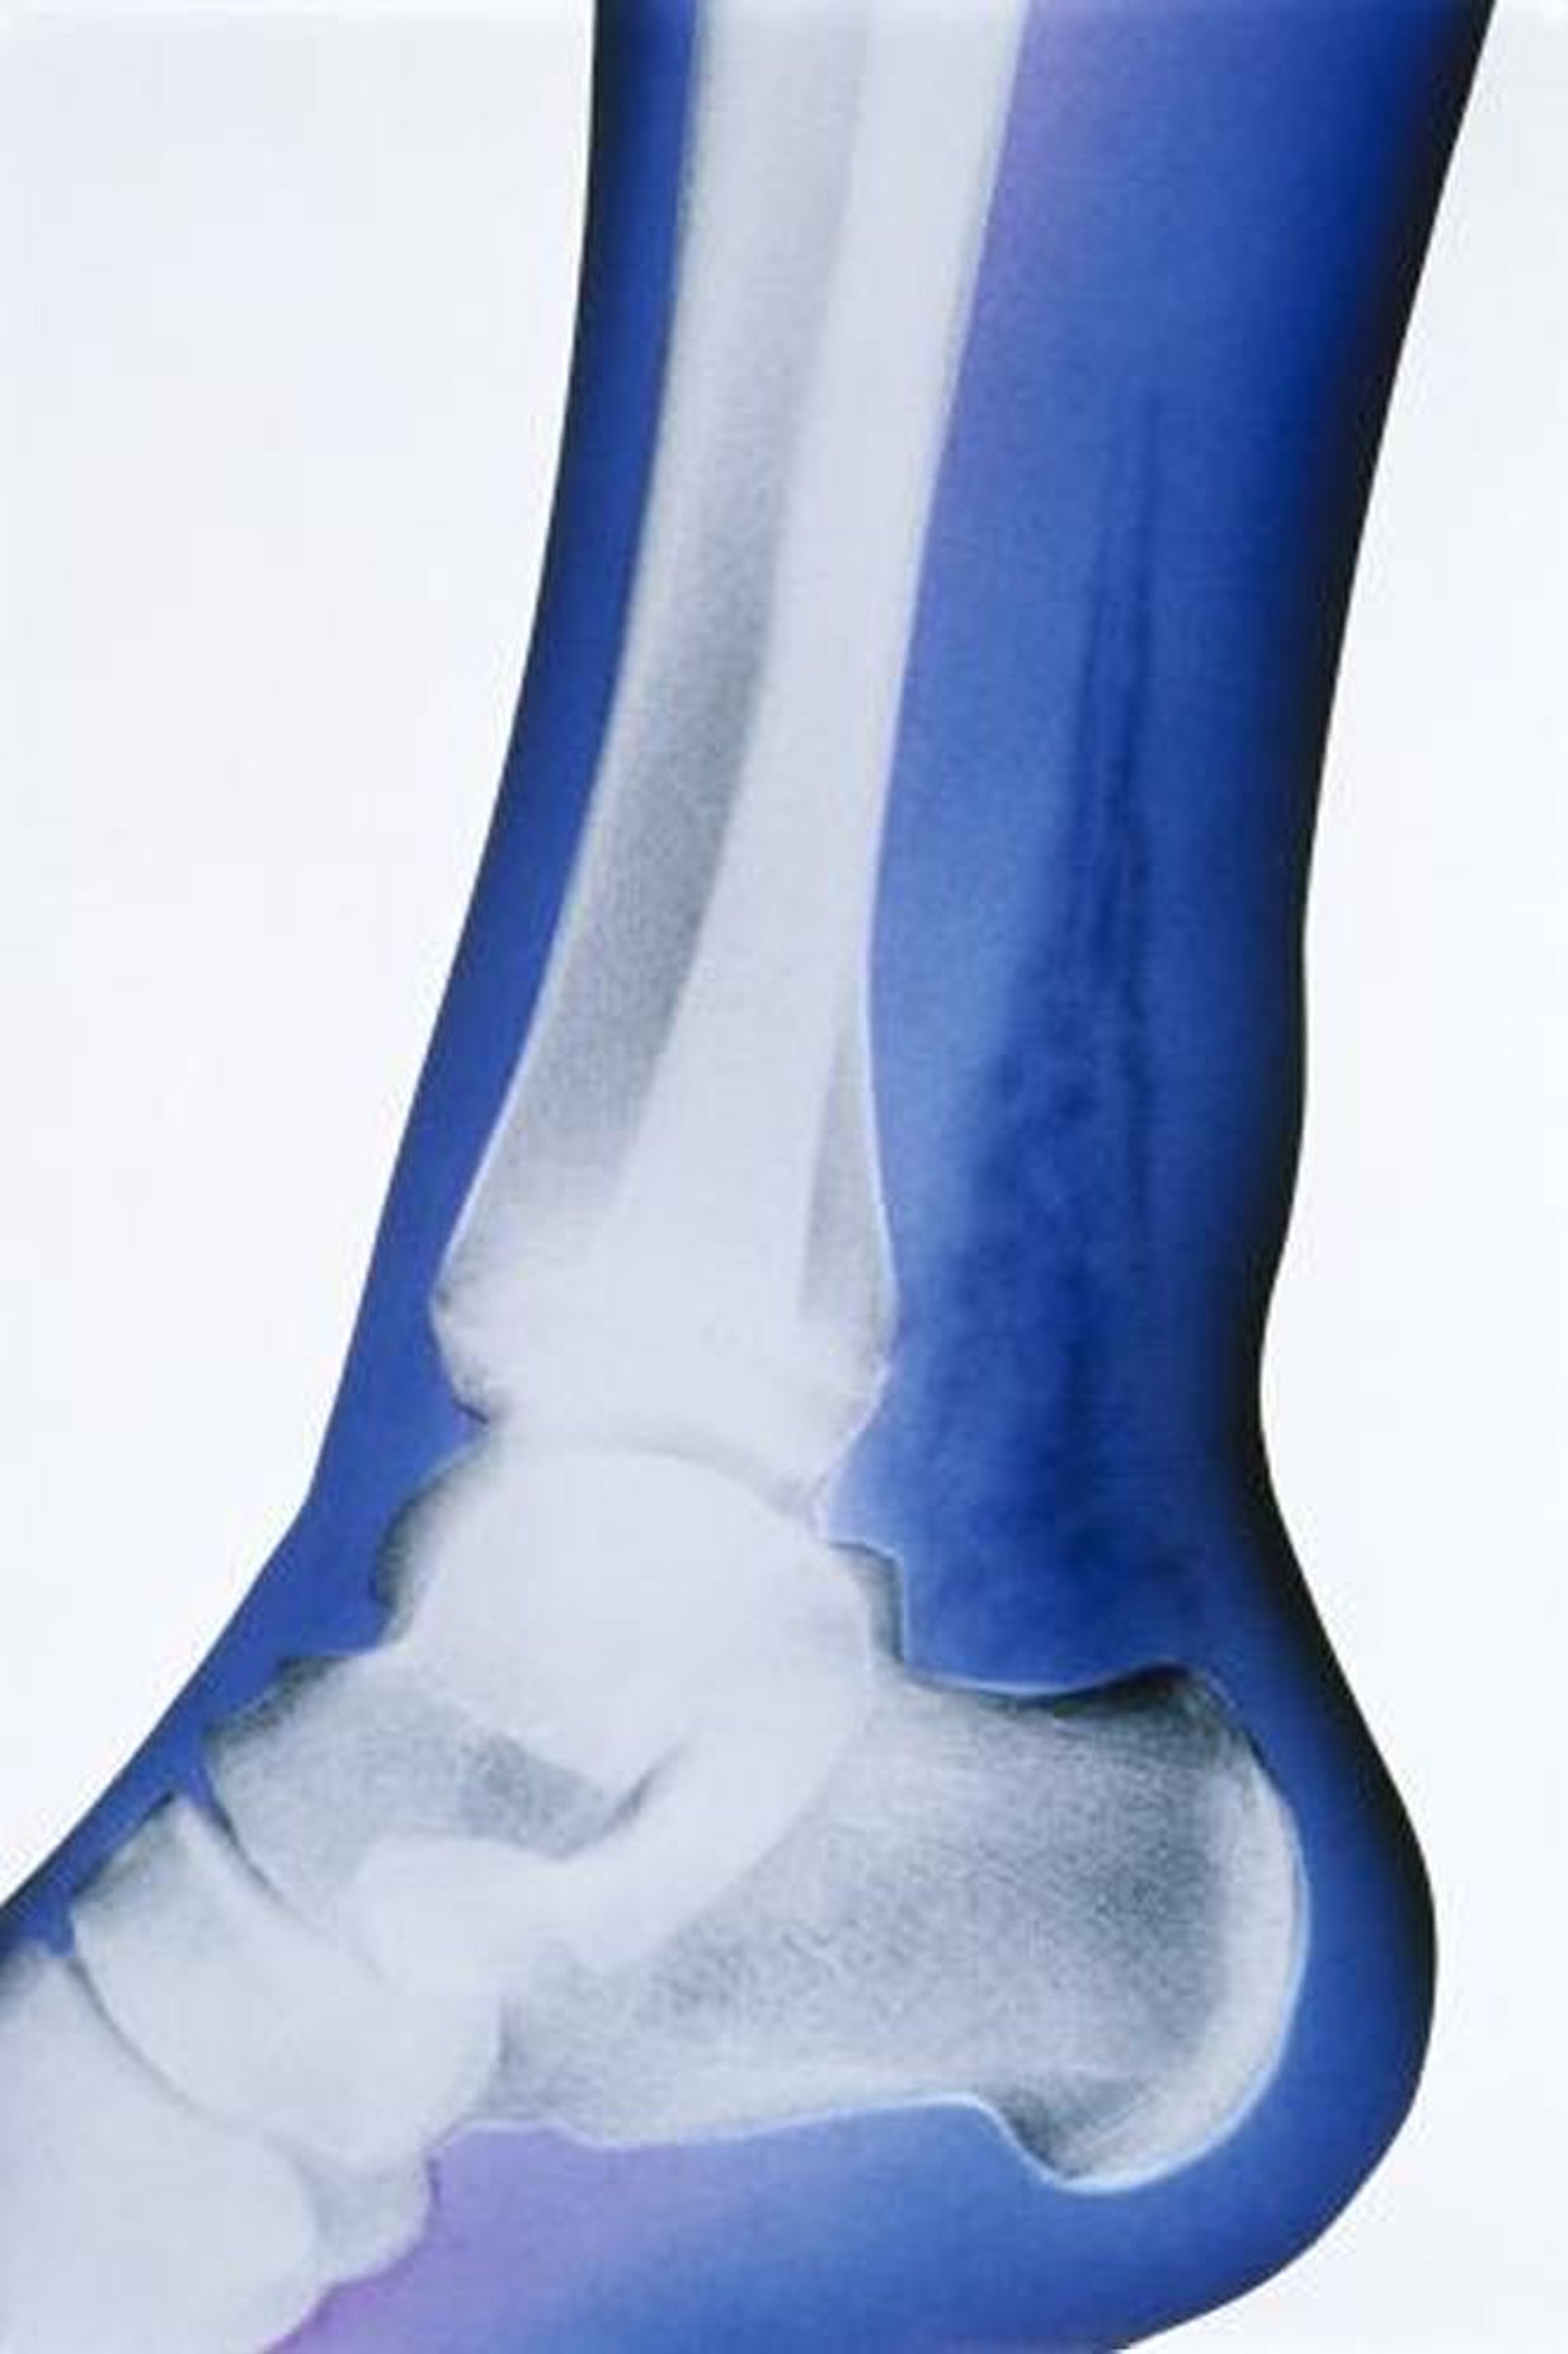

Nhiễm trùng dưới da hoại tử (X-quang)

Trong phim X-quang có màu nhân tạo này, dấu hiệu nổi bật là sự hiện diện của khí trong mô mềm, được biểu thị bằng độ thấu quang cao ở trước xương gót và sau xương chày, xương mác.